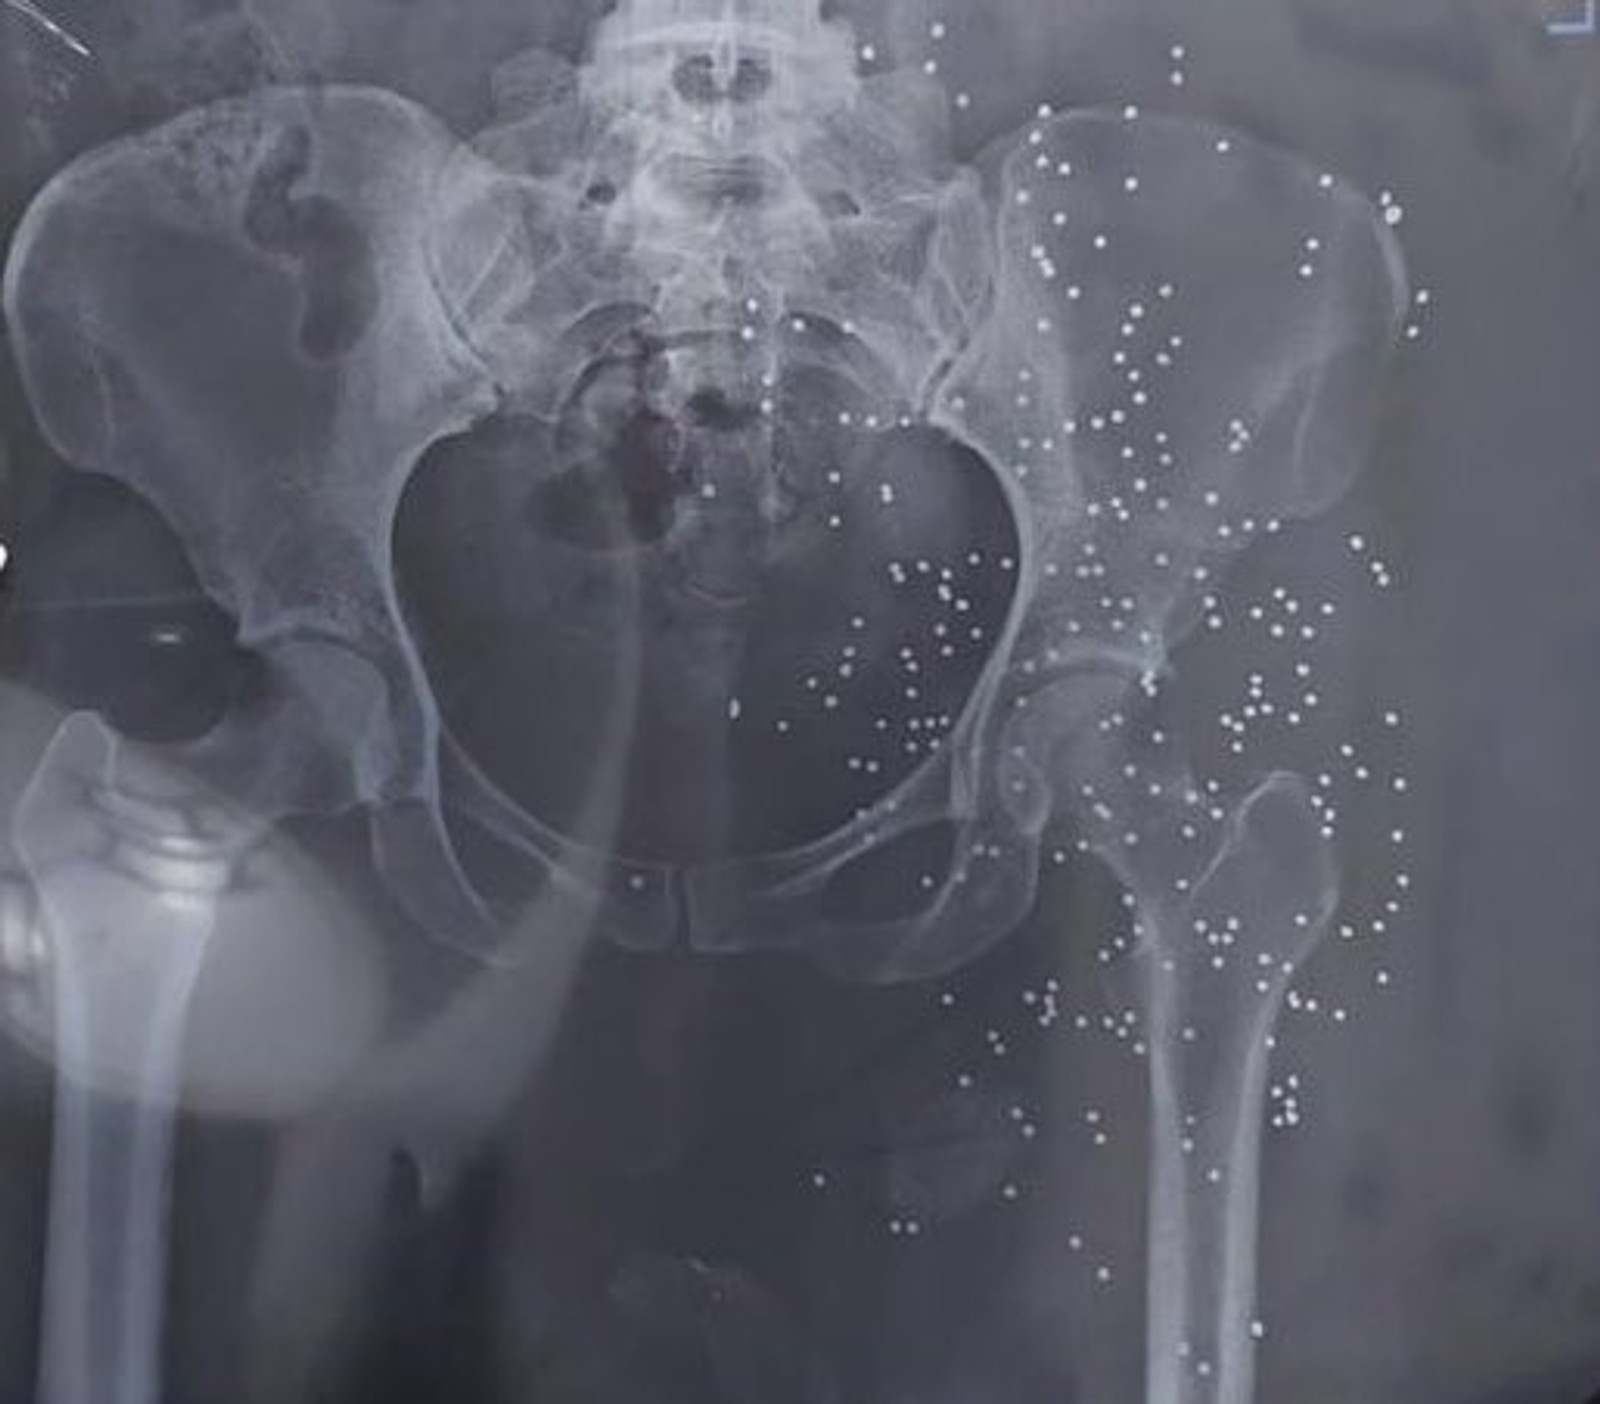

In addition to photos and videos of the injuries, the batch includes dozens of x-ray images and CT scans of pellets and slugs in the head, neck, chest and legs of the protestors. The Islamic Republic has killed many protesters with rubber bullets and metal pellets and blinded so many others.

The regime’s security forces have been extensively using cartridges of shotshell loaded with numerous small balls or birdshots, or medium-sized buckshots as well as single large solid projectiles known as a slug to quash the nationwide protests, ignited by the death in custody of 22-year-old Mahsa Amini in September 2022.

Although some of the photos and videos were deleted by twitter, the remaining ones are enough to see a pattern of the regime’s systematic targeting of faces and genitals of the demonstrators.